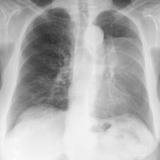

LUL Collapse Case 3 PA

Date: 02/19/2004

Views: 3336